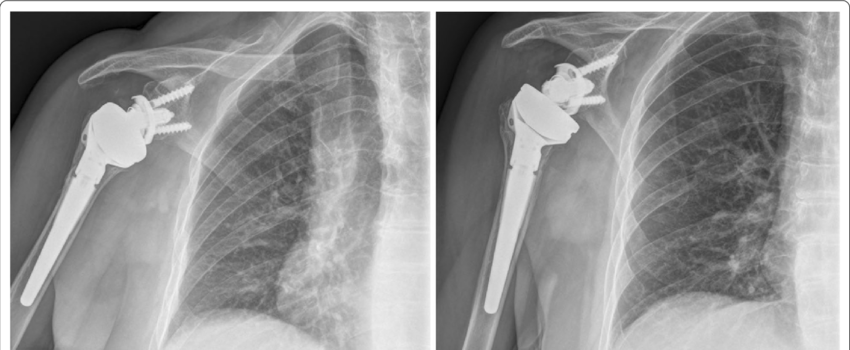

In a standard shoulder replacement, the ball of the joint is replaced with a prosthetic ball and the socket with a prosthetic socket. In reverse shoulder arthroplasty, the positions are switched — a metal ball is attached to the shoulder blade and a socket is attached to the upper arm bone. This design allows the deltoid muscle, instead of the damaged rotator cuff, to power the arm.